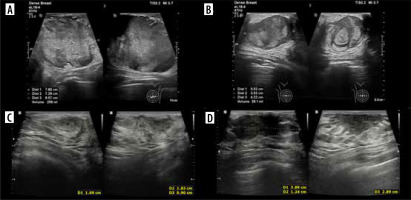

The patient was admitted to our centre for further diagnosis and treatment. On US almost complete involvement of both breasts by heterogeneous, irregularly vascularised nodules was described; in the left breast, the largest ones were located centrally, and had approximately 78 × 73 × 86 mm on the left and 50 × 35 × 42 mm on the right (Figures 9A and B). Additionally, numerous enlarged lymph nodes and a metastasis in the mastoid attachment of the right sternocleidomastoid muscle were found. WB-MRI revealed multiple lesions consistent with metastases throughout the body. On PET-CT, all of them showed increased metabolism of 18F-FDG.

Two ultrasound (US) examinations of breast metastases in Patient no. 4. A, B) Initial examination in our centre. A) The largest nodule in the left breast. B) The largest nodule in the right breast. C, D) The second US after the 4th cycle of chemotherapy. Partial regression of the lesions. C) Nodule in the left breast. D) Nodule in the right breast

The patient was qualified for chemotherapy (VAC), and partial regression of the metastatic and primary lesions was initially achieved (Figures 9C and D).